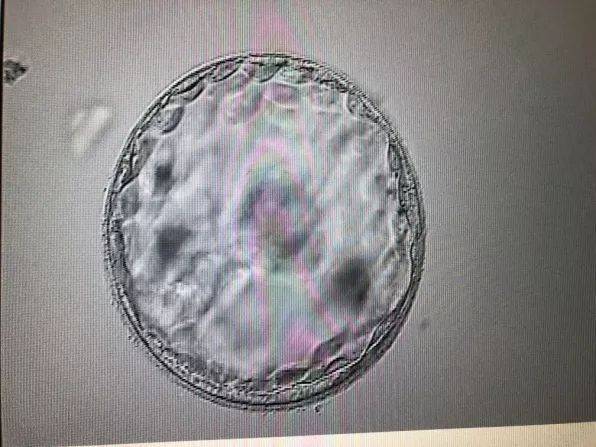

1. 超声波检查

超声波检查是目前最准确、最安全的方法来预测宝宝的性别。通过观察宝宝的生殖器官,医生可以判断出宝宝的性别。